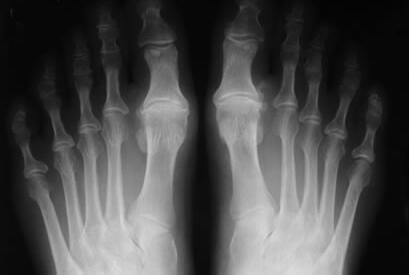

El Hallux Rigidus es una patología que impide la dorsiflexión de la articulación del Hallux (dedo gordo del pie).

Se caracteriza por una artrosis osteofítica, degenerativa y anquilosante de la primera articulación metatarsofalángica. El Hallux Rigidus es uno de los problemas más frecuentes del primer dedo del pie.

Debido a los cambios estructurales y a la pérdida de cartílago, se produce una disminución progresiva de la movilidad en la primera articulación metatarsofalángica, que va generando rigidez de una forma progresiva.